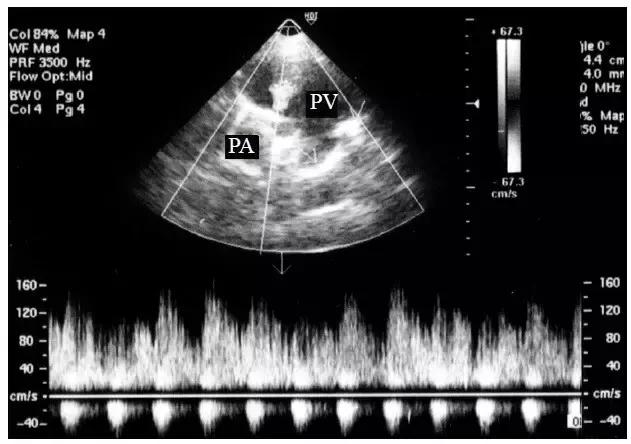

4.脉冲多普勒取样为高速双峰血流频谱。

5.在闻及连续性杂音的部位探查,往往可显示肺动脉内五彩镶嵌血流射入呈瘤样扩张的肺静脉内(图1),连续多普勒在瘘口处取样为连续性湍流频谱(图 2)。

图2 肺动静脉瘘的频谱多普勒表现